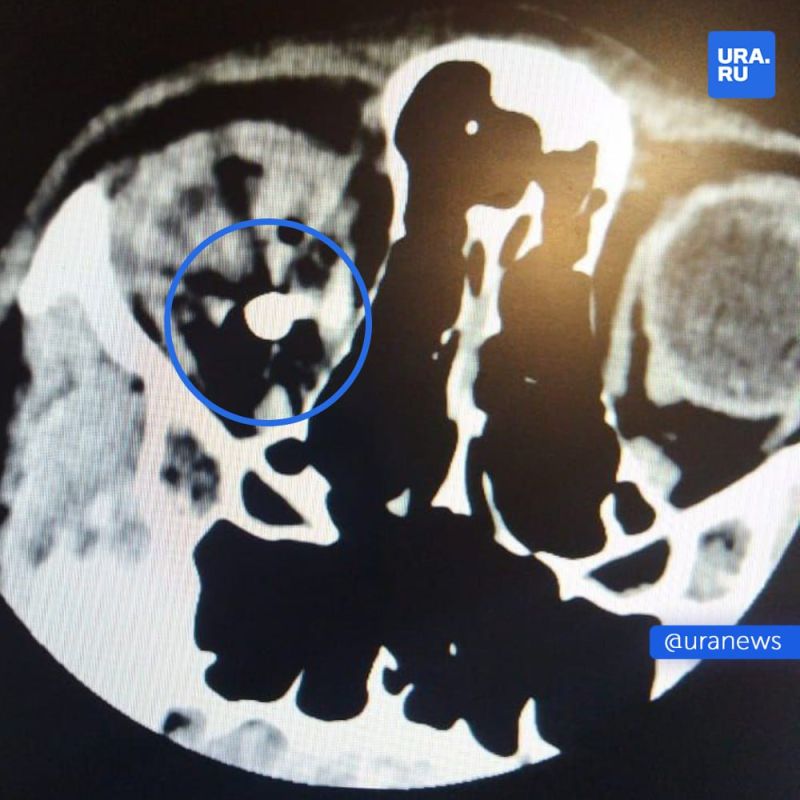

13-летний подросток выстрелил другу в глаз из пневматики — врачи до сих пор не могут достать пулю из головы.